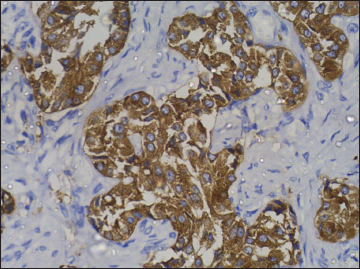

| Figure 10 Immunohistochemistry on subcarinal node showing strong positivity for chromogranin